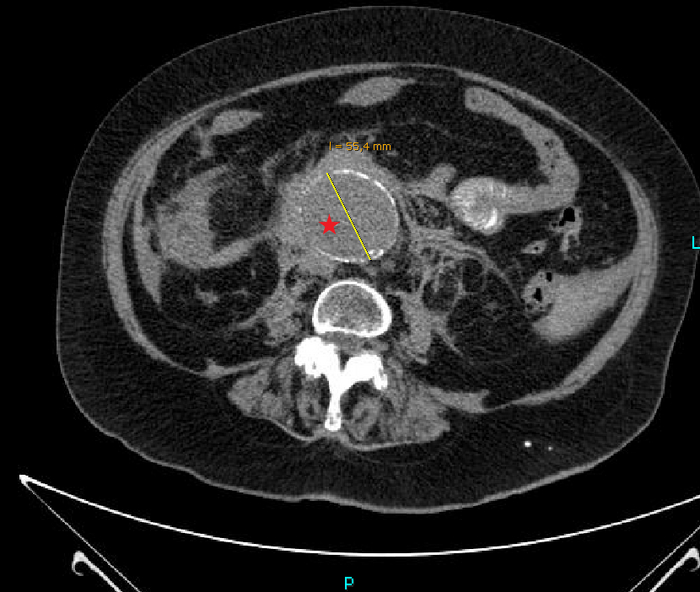

Переключаемся на "костное" окно (позволяет луче оценить кости и прочие плотные структуры), где реально видим "металлический" предмет в просвете правого нижнедолевого бронха:

сагиттальная, аксиальная и корональная реконструкция